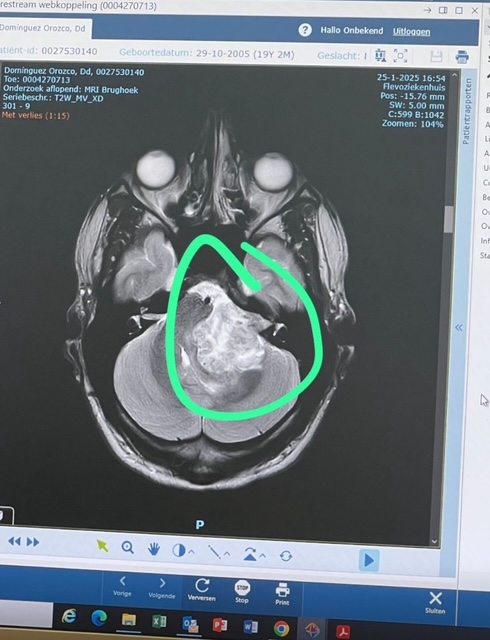

Dylan kampte al langer met gehoorproblemen, maar had nooit gedacht dat een tumor de reden hiervan zou zijn. Zo is hij rapper en veel in de studio, maar ook op het podium te vinden. Daarom dachten de dokters en hijzelf ook dat het zijn grote passie was die de oorzaak van zijn gehoorproblemen was. Maar Dylan begon steeds minder te horen en kreeg uiteindelijk een MRI-scan, waaruit bleek dat het om meer dan alleen gehoorproblemen ging. Dylan heeft een brughoektumor achter zijn oor. "Normaal maakt het niet zoveel uit, omdat het een goedaardige tumor is. Bij mij is de tumor alleen vier en een half centimeter groot, waardoor die is doorgegroeid naar mijn hersenen en mijn gezichtszenuw heeft aangetast. Omdat de tumor zo snel is gegroeid, moeten we hem zo snel mogelijk verwijderen", vertelt Dylan. Normaliter heeft de operatie een wachttijd van zo'n vier à zes maanden, maar Dylan kreeg te horen dat de tumor in zijn geval binnen vier weken weggehaald moet worden.